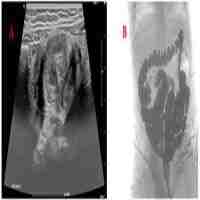

| Abstract | Vertical transmission of SARS-CoV-2 from mother to fetus is widely accepted. Whereas most infected neonates present with mild symptoms or are asymptomatic, respiratory distress syndrome (RDS) and abnormal lung images are significantly more frequent in COVID-19 positive neonates than in non-infected newborns. Fatality is rare and discordant meta-analyses of case reports and series relating perinatal maternal COVID-19 status to neonatal disease severity complicate their extrapolation as prognostic indicators. A larger database of detailed case reports from more extreme cases will be required to establish therapeutic guidelines and allow informed decision making. Here we report an unusual case of a 28 weeks' gestation infant with perinatally acquired SARS-CoV-2, who developed severe protracted respiratory failure. Despite intensive care from birth with first line anti-viral and anti-inflammatory therapy, respiratory failure persisted, and death ensued at 5 months. Lung histopathology showed severe diffuse bronchopneumonia, and heart and lung immunohistochemistry confirmed macrophage infiltration, platelet activation and neutrophil extracellular trap formation consistent with late multisystem inflammation. To our knowledge, this is the first report of SARS CoV-2 pulmonary hyperinflammation in a preterm newborn with fatal outcome. |